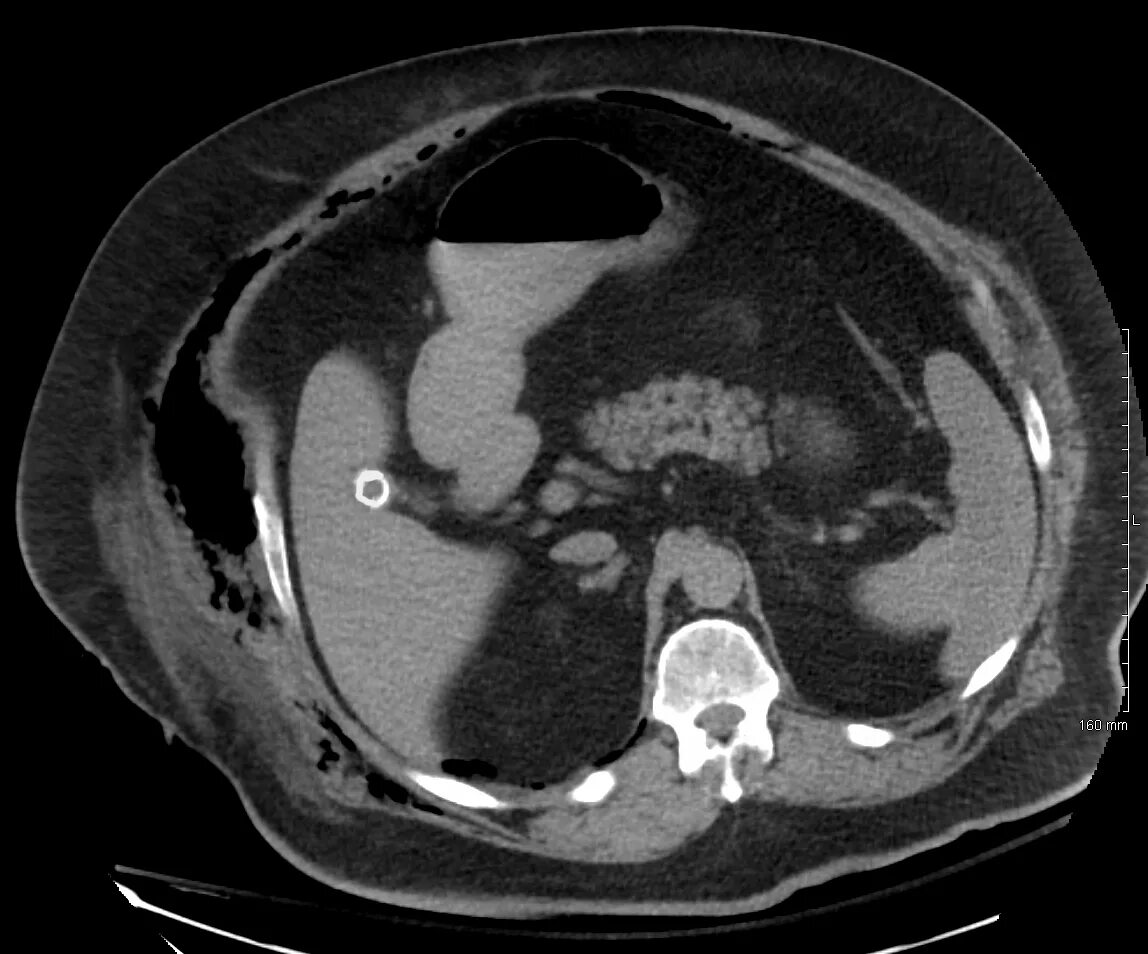

Кт тканей